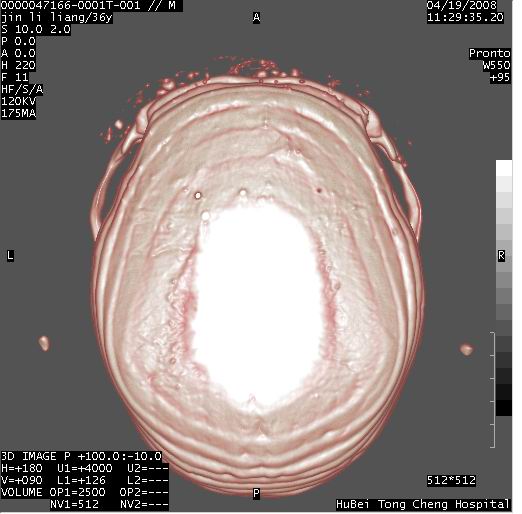

患者 男,36岁。头面部“土炮”炸伤。pe:面目全非,伤口流血不止。

临床诊断:头面部外伤。

颅脑ct轴位平扫(层厚、层距均为10mm),图像如下: